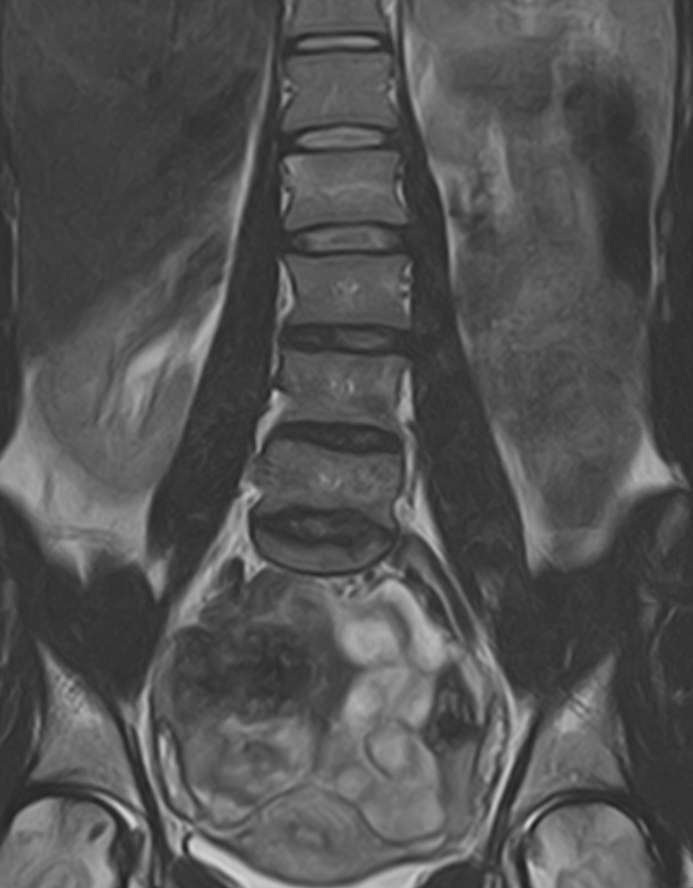

В клинике «Доступная медицина» проводится комплексное обследование позвоночника, включающее два протокола сканирования — МРТ грудного и поясничного отдела.

Магнитно-резонансная томография является наиболее точным и эффективным способом диагностики различной патологии позвоночного столба. Метод позволяет визуализировать не только костные структуры позвонков, но и оценивать состояние спинного мозга на исследуемом уровне, нервных корешков, связочного аппарата и окружающих мягких тканей. МРТ сочетает в себе высокую точность и информативность, при этом является безболезненной, неинвазивной и безопасной процедурой, так как во время исследования не применяется вредное рентгеновское излучение. В основе метода лежит использование магнитного поля, которое не оказывает негативного действия на организм человека.

Комплексное обследование грудного и поясничного отдела позвоночника обычно требуется в тех случаях, когда имеется подозрение на множественное поражение позвоночного столба, которые могут быть вызваны опухолевыми, воспалительными или дегенеративными заболеваниями позвоночника.

Магнитно-резонансная томография, предусматривающая обследование средней и нижней части спины, охватывает область семнадцати позвонков: двенадцать из них формируют заднюю стенку грудной клетки, пять находятся между ребрами и крестцовым отделом. Исследование позволяет визуализировать:

МРТ грудо-поясничного отдела позвоночника обладает высокой чувствительностью и специфичностью. Она позволяет не только определять границы патологических очагов, но и решает более сложные диагностические задачи. МР-сканирование является обоснованным методом выбора при врожденных аномалиях развития, синдроме фасеточных суставов, межпозвонковых грыжах, остеомиелите, заболеваниях спинного мозга, вертебральных опухолях.